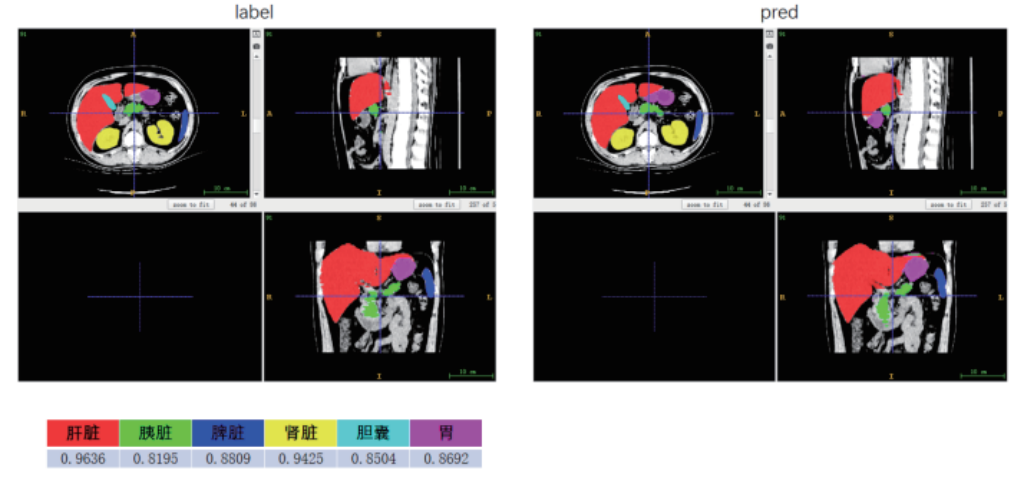

腹部CT图像多器官分割案例